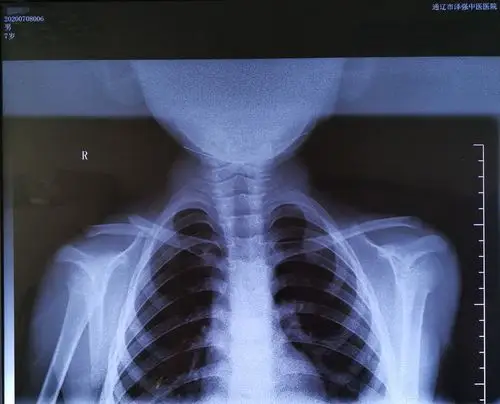

6月3号被汽车撞伤,锁骨骨折!医生建议保守治疗,用8字带绑了6天!

左锁骨骨折

锁骨骨折

一岁五个月的孩子锁骨折断错位 附图